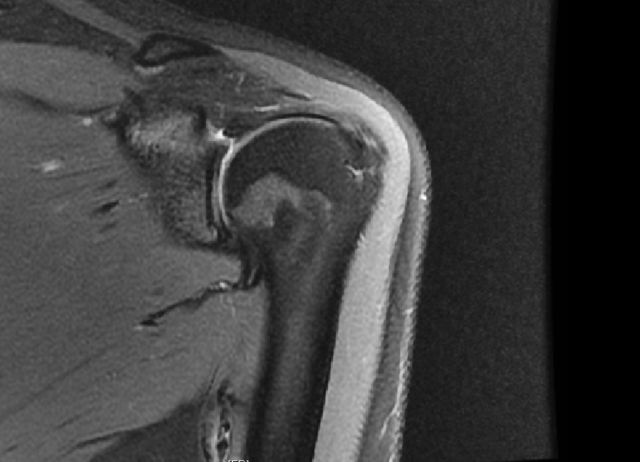

从肩甲盂上部撕裂

从此片可以看到上盂唇和肱二头肌建,从肩甲盂的上部撕裂